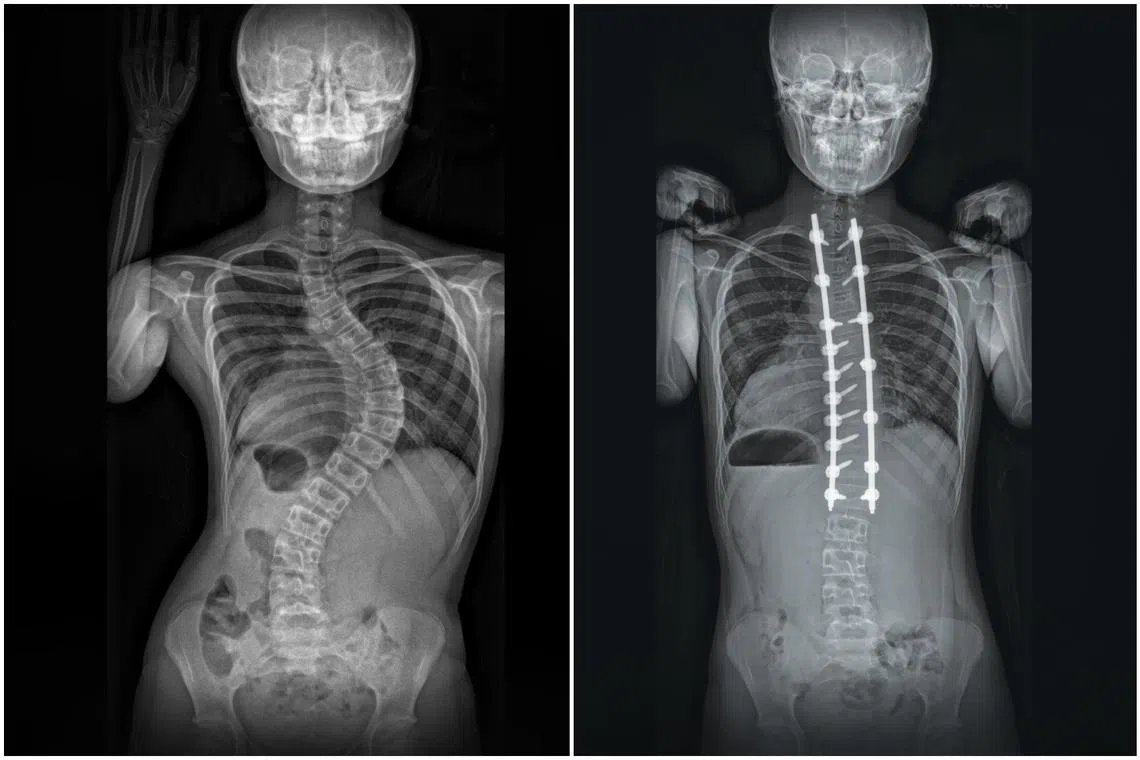

Jayna Leong, who was diagnosed with scoliosis, underwent spinal fusion using special rods, hooks, screws and bone graft to carefully straighten the curved portion of her spine.

SINGAPORE - Spine surgeons in the public and private sectors have seen a surge in the number of teenage girls needing surgical intervention to correct severe scoliosis, or curvature of the spine.